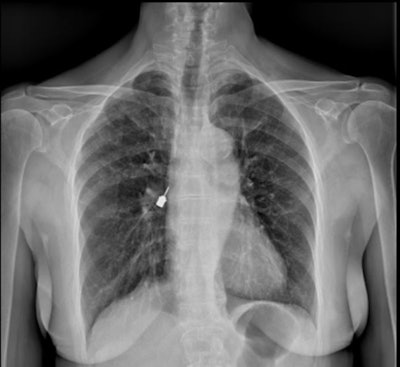

Then a CT scan was completed to get a precise location of the drill head. The scan confirmed that the drill head was in the intermediate bronchus and extended into the inferior bronchus on the right side.

Figure 2: Thoracic CT scan showing the drill head located in the right intermediate and right lower bronchi. (A) coronal view (B) axial view.